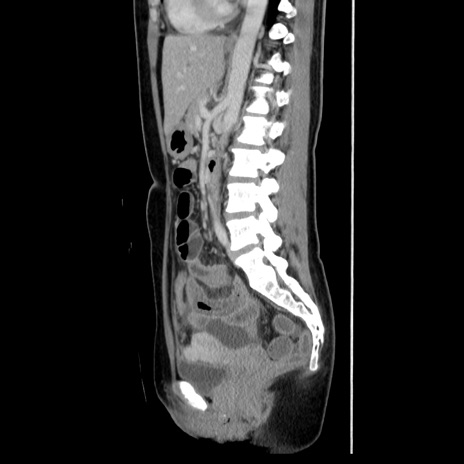

症例39(矢状断像)

【症例】40歳代女性

【主訴】上下腹部痛

【現病歴】2日目から下腹部痛あり。夜間は痛みで眠れなかった。昨日より上腹部痛と下痢が出現。臥位で痛みは軽快したため、休んでいた。本日になって臥位でも立位でも痛みが強くなってきたため救急要請。

【既往歴】子宮内膜症

【身体所見】部:平坦・軟、左上下腹部に圧痛あり、反跳痛あり。

【データ】WBC 21800、CRP 26.78

CT